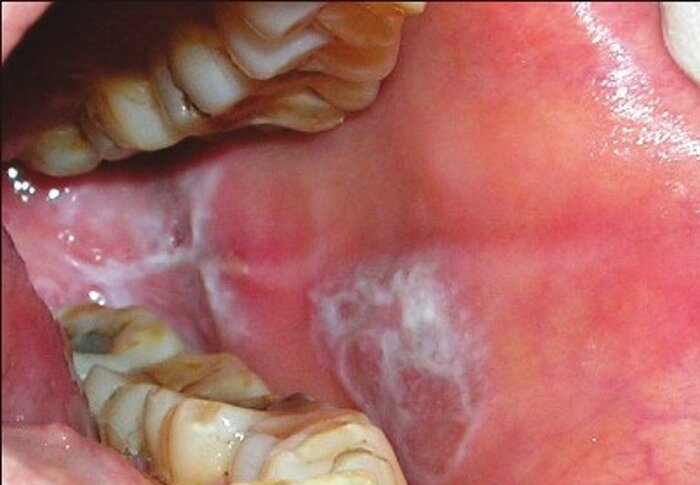

یکی از کارشناسان سلامت خراسان شمالی با اشاره به عوارض جسمی و روانی بی تی می گوید: نیکوتین موجود در بی تی از طریق مخاط دهان جذب و باعث بدرنگ شدن دندانها شده و باعث سرطان دهان و حنجره میشود.

کریم بهمن می افزاید: جدای از ایجاد بیماریهای لثه، ساخارین موجود در آن عامل بیماریهای کلیه و سرطان روده بزرگ است و عوارض گوارشی متنوعی برای فرد ایجاد میکند.